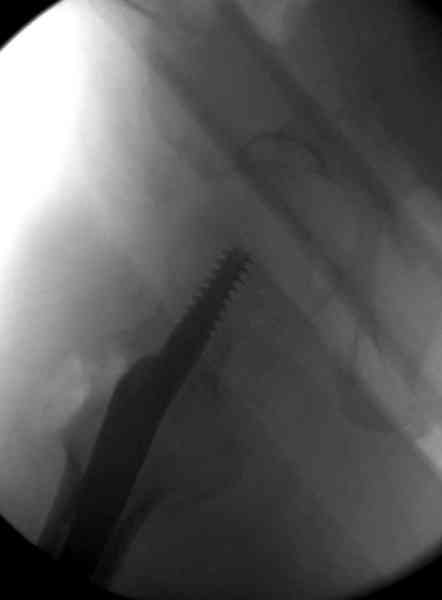

Во время операции ни стол ортопедический,ни ДРУ не применялось (думалось, что сделают все на руках!)

Изначально была выбрана не правильная точка введения стержня, в связи с чем в конце, я подчеркну, в конце операции произошло из-за напряжения между прокимальным концом канала бедра и стержнем разрушение в/3 бедра.

Проволока наложена потому, что при введении штифта не прошли эту зону римером и произошли сколы на концах отломков.

Под ЭОП во время операции такого смещения не было. Мы бы конечно не отпустили этого больного с такой картиной (сами бы что-то сделали или к вам отпр).